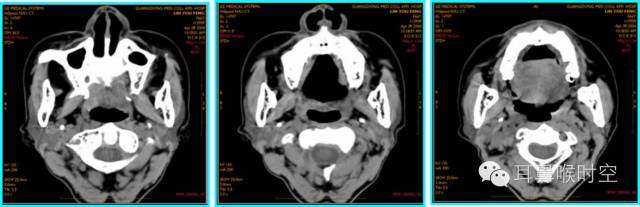

儿童腺样体肥大依据CT 表现分为3 型:

CT表现:

为鼻咽顶后壁增厚,形成肿块

前缘平直或略凹陷,堵塞后鼻孔

鼻咽腔变形、狭窄,上气道变窄。

CT 表现:

除Ⅰ型外

同时有上颌窦、筛窦黏膜增厚,窦腔变窄等慢性鼻窦炎表现及鼻甲肥大和/或鼻中隔偏曲

除Ⅰ型的CT表现外

还有咽鼓管咽口粘连狭窄及中耳乳突积液,即分泌性中耳炎表现。

标准CT 轴位像:

鼻咽气腔均不同程度变形变窄(图7,8) , 不规则形,横条形,完全闭塞。

增大的腺样体呈软组织密度,均匀一致,与头长肌相近,呈弥漫性肿块形(图9)、嵌入鼻后孔肿块形(图10)、单侧肿块形(图11)。

静脉增强扫描呈轻-中度强化。